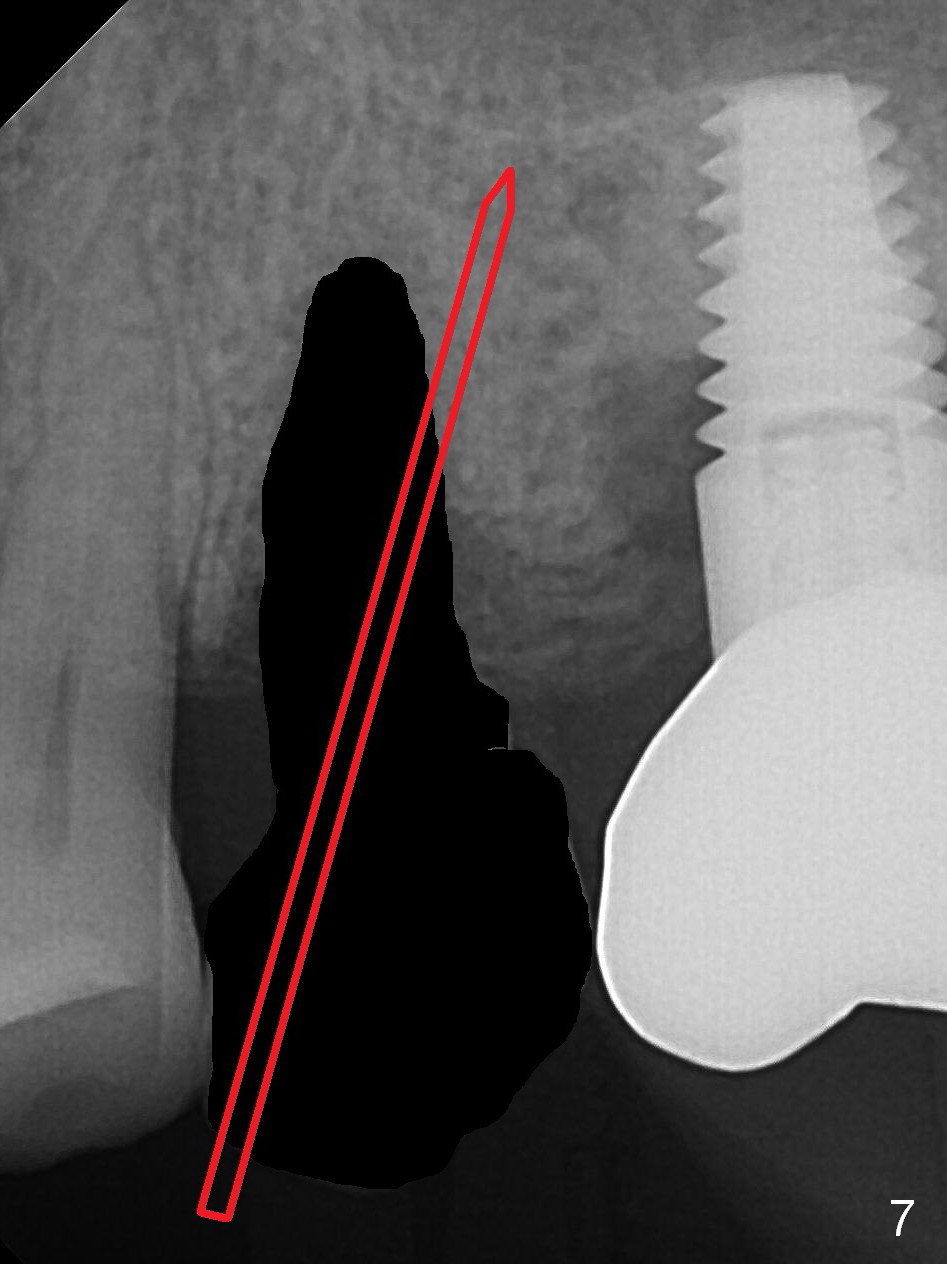

To compensate for bruxism, the implant at #13 should be as large and long as possible. After extraction (Metronidazole), take PVS impression of the socket. Start osteotomy in the distal wall of the socket (Fig.7 red). The initial depth is 11 mm (gingival level). Increase the depth once the trajectory is confirmed (Fig.9). After implant placement (Fig.8 green), place bone graft (red circles) in the mesial portion of the socket as well as in the coronal portion of the implant at #14 (incision). Use a healing abutment (pink), collagen plug (yellow) and suture to close the socket opening.